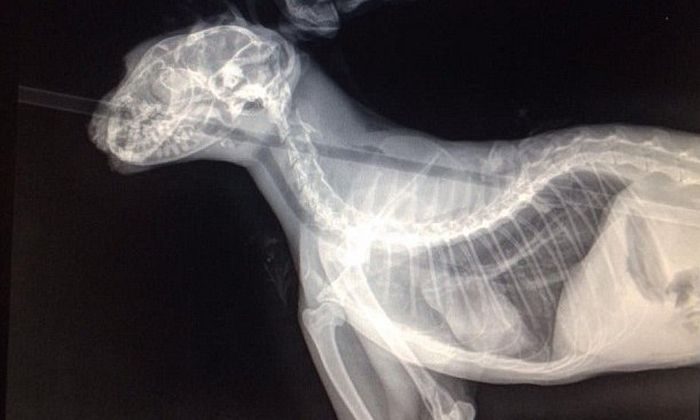

Животное, которое, согласно заключению ветеринара, является годовалым представителем сиамской породы окраса линкс-пойнт, было доставлено в ветеринарную клинику Вашингтона для лечения. Ветеринар Джейс Кинг первым делом провел рентгенологическое обследование и выяснил, что прошившая кота стрела каким-то чудом не задела жизненно важных органов животного, хотя и прошла в опасной близости от мозга, сердца и легких.

Стрела, вошедшая в голову Колчана между переносицей и ртом, проткнула язык, прошла через пищевод и вышла между лопатками. В четверг Колчан перенес операцию, в ходе которой стрела была извлечена из его тела. Доктор Кинг зашил дыру в пронзенном небе и сшил разрезанный язык.

Стрела оставила у носа Колчана отверстие диаметром 1,3 сантиметра, а также рану в пищеводе, до которой врачи не смогли добраться, заверив, что животное сможет залечить ее самостоятельно